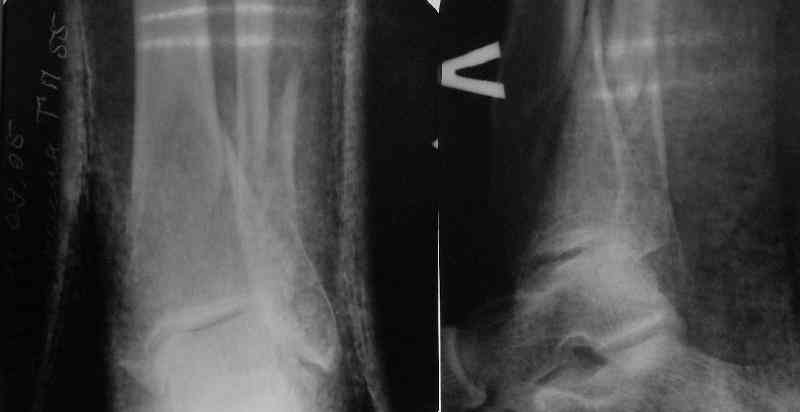

A typical case is attached, also an image with intra-op reduction obtained by a small wire distractor, in the moment of insertion a Poller wire in AP direction. Fixation by a SIGN nail. Despite the fibula was not fixed healing was obtained with the unchanged alignment.

fibula. Angular stability of the tibia is provided by insertion of more than two conventional medial-lateral locking screws. To maintain the position of the fibula perQ insertion of a single position screw often could be enough. I bet the articles didn't analyze the options.

In delayed cases acute length restoration performed only in the tibia may leave the fibula shortened thus change the mortise. So it is reasonable to restore length of both bones simultaneously by distractor and fix the fibula not with open reduction and plating but just by a single perQ screw. Example attached.